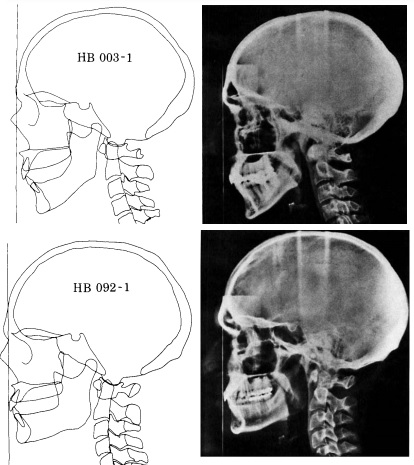

View attachment 144957

That's what I can do. I am not a professional scientist. If I was I'd do more deep analizys of things. I'd make a x ray of head and neck of balding men, compare it to controls. Check their scalp if It's stiffer compared to controls. The next thing I will do is take a balding men with me, massage his neck and surrounding muscles of the head to relax them and If he experiences hair regrowth then - I am right.